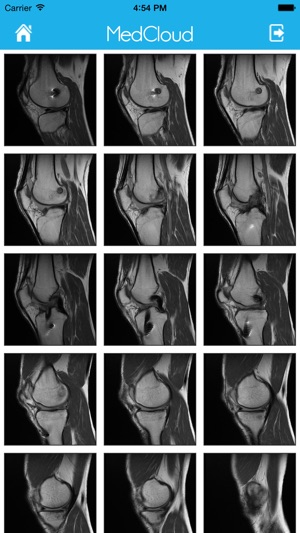

Através de uma plataforma centralizada, integrável e interativa, a MedCloud oferece conectividade e compatibilidade com todos os tipos de mídia, modalidades de exames e protocolos de integração voltados para sistemas de saúde.

Clinicas, hospitais, laboratórios, médicos, dentistas e demais empresas do segmento de saúde podem compartilhar trivialmente seus exames e informações de saúde com profissionais de saúde e pacientes, utilizando apenas uma conexão de Internet como requisito. Médicos, dentistas e pacientes podem interagir e compartilhar seus exames entre si, de forma prática e simples, além receberem opiniões de diferentes profissionais de saúde e manterem seu histórico médico online e seguro.